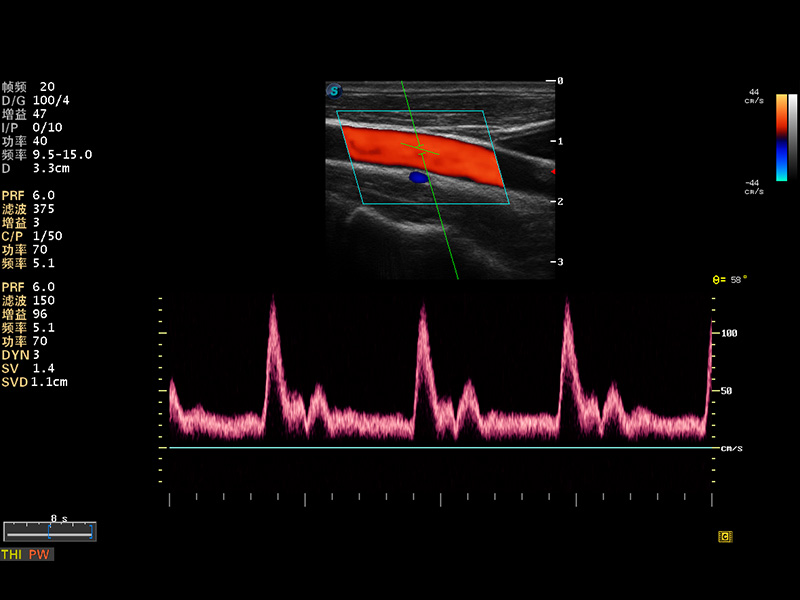

颈动脉PW